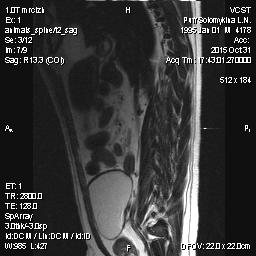

Мопс 6 лет - межпозвоночная грыжа - 10002.jpg

Мопс 6 лет - межпозвоночная грыжа - 10002.jpg (14.06 КБ) 768 просмотров